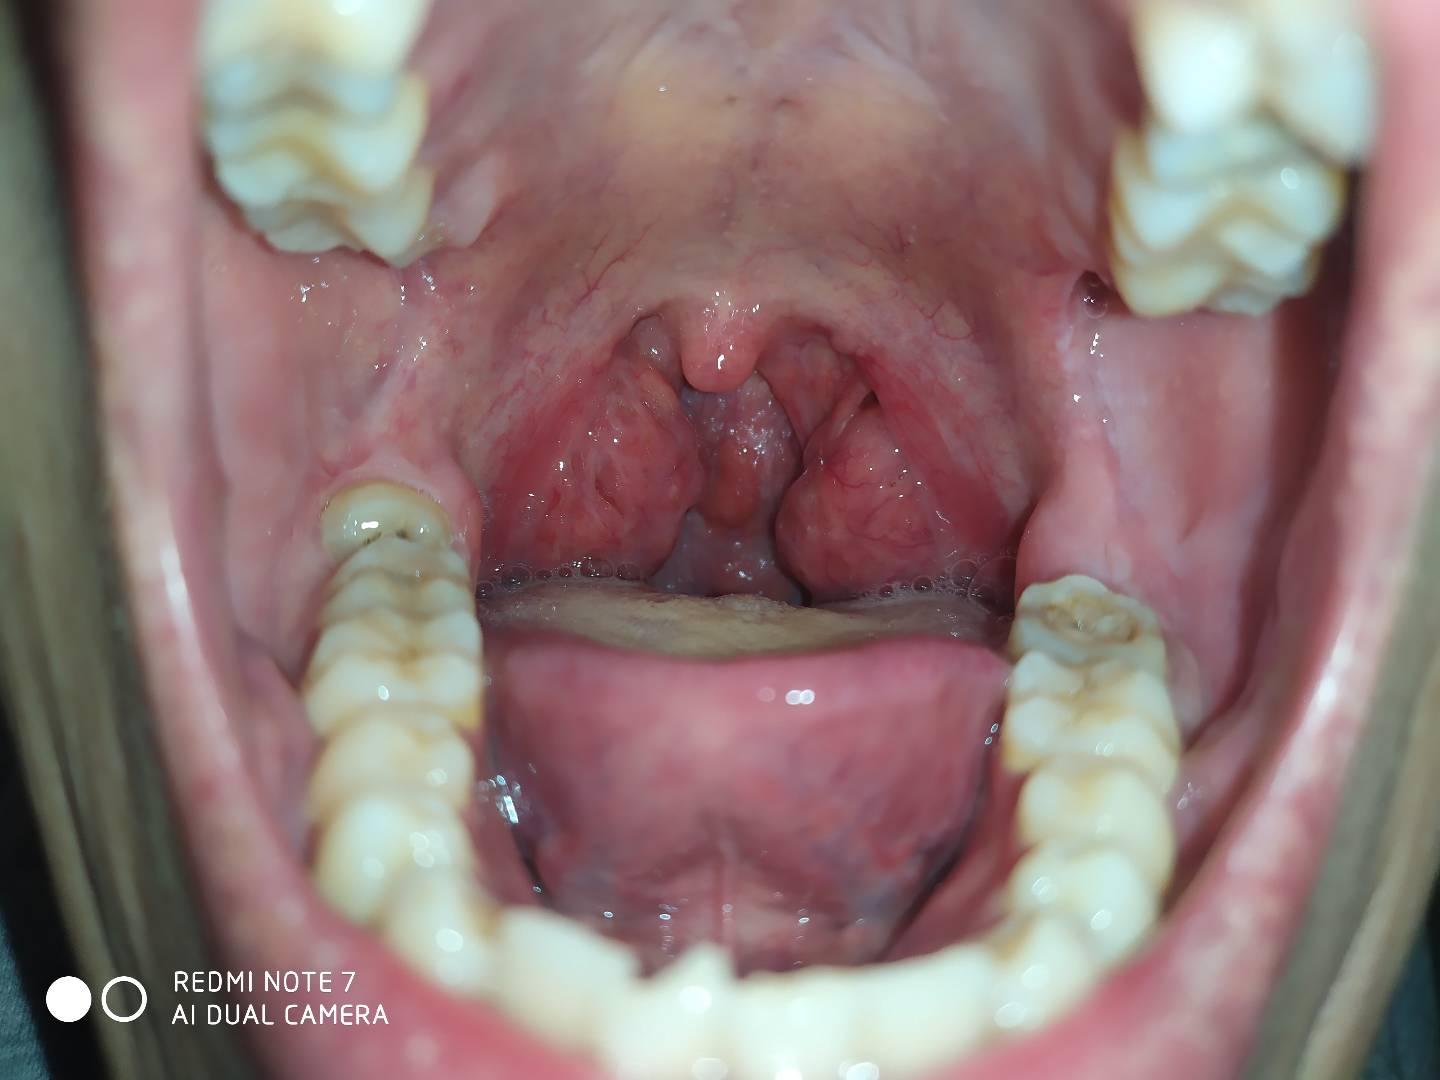

喉咙上的小舌头结构图

喉咙上的小舌头结构图,人体构造五脏六腑位置

今天看嗓子的时候觉得小舌头变小了.你们手术以后也会有这种情况吗?

舌头根部还有豆?是不是有什么问题啊

问 20 目前是咽喉痒咳嗽,至今发现舌头上变黑了!是什么情况啊?

这个无需要质疑,这个属于喉咙疱疹,看看这个舌苔,湿热内盛.

口腔结构高清示意图

嗓子图片内部图片大全

喉咙的结构图片

咽喉炎图片大全